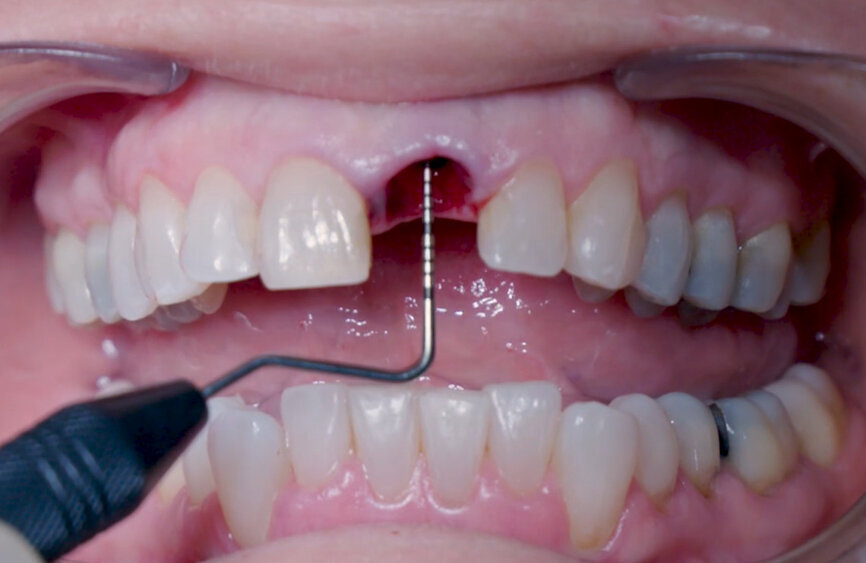

Fig. 12: Final implant position assessment in relation to gingival margins.

Fig. 16: Granule condensation with surgical probe.

Intra-sulcular incisions were performed to release the marginal gingival fibres to allow a minimally invasive extraction. The socket was carefully cleaned to remove any ligament and debris left. Special attention was given to assessing the alveolar wall integrity. A distance of 3 mm was observed between the gingival margin and the labial wall margin. Implant bed preparation considered a medium-density bone workflow, starting with the needle drill aimed at the palatal wall to create an entry point for the next drills, creating an osteotomy that allows for a greater area of implant engagement (Fig. 5). The Ø 2.2 mm pilot drill was used to the respective implant length planned, followed by the use of an alignment pin to check the 3D orientation (Figs. 6 & 7). The Ø 2.8 mm and Ø 3.2 mm drills were used to finalise the osteotomy (Fig. 8). The site was then properly probed to assess for possible wall perforation. A 4 × 14 mm implant was placed, starting with the surgical handle engaging the apical part of the implant, following the same orientation as that of the needle drill and correcting the implant direction as it moved within the osteotomy (Figs. 9 & 10). Primary stability (45 Ncm) was achieved at the final position. After placement, the implant position was verified horizontally with an occlusal mirror and vertically with a surgical probe, and at this point, the abutment gingival height was selected (Figs. 11 & 12). A healing abutment was placed on to the implant (Fig. 13) to protect the connection so that granular bone substitute (Straumann XenoFlex) could be applied in the gap between the implant and labial wall. This was gently compacted in with the 2.8 mm side of the surgical probe (Figs. 14–16). Collacone (botiss biomaterials) was used to keep the bone granules away from the gingival margins in order to avoid softtissue fenestration and fibroblastic infiltration (Figs. 17 & 18).